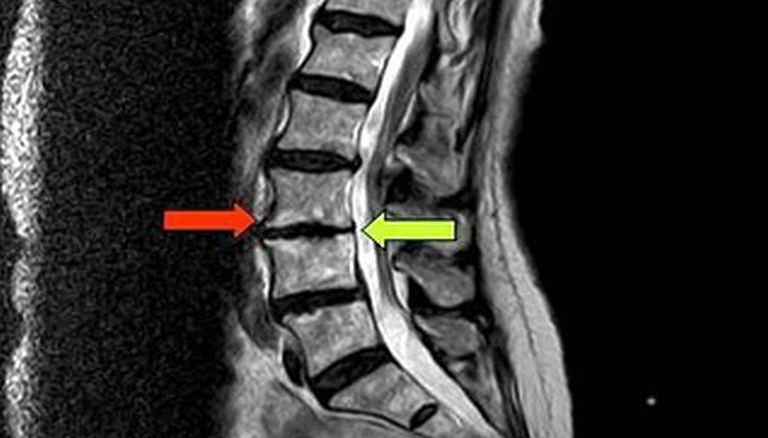

Диска с7 th1

Диска с7 th1 111 фотографий